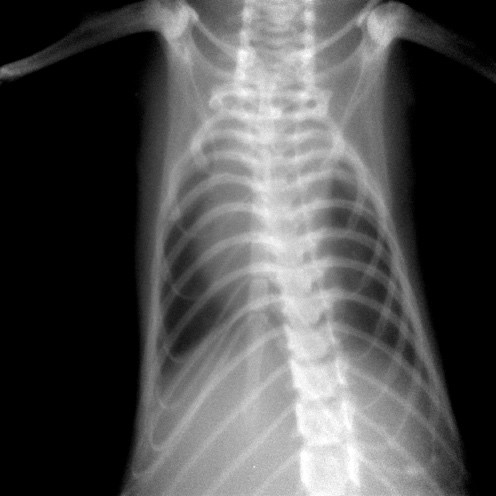

The PAM mouse model study was inspired by a patient seen by Dr. McCormack in 2011 at UC Medical Center. The woman had been diagnosed with PAM as a child in Jordan and developed exertional dyspnea at the age of 54, a typical pattern for PAM. Chest examination revealed bibasilar crackles, pulmonary function tests revealed mild restriction and reduced diffusing capacity, and a six-minute-walk test revealed normal exercise capacity with mild exertional desaturation to 88%.1 Chest X-ray showed fine hyper dense lower lung zone nodular opacities, and computed tomography of the chest showed symmetrical lower lobe predominant micronodular calcifications along bronchovascular bundles and interlobular septal thickening, findings pathognomonic for PAM.1

Chest x-ray of patient with PAM showing hyper dense, fine nodular opacities in the lower lung zones1.